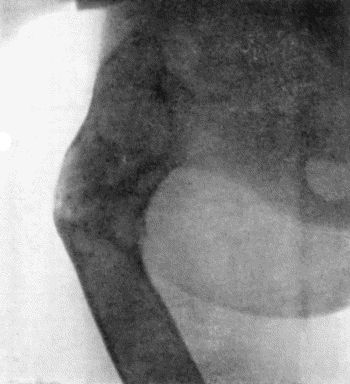

71.Radiogram of Aneurysm of Aorta 303

72.Sacculated Aneurysm of Abdominal Aorta 304